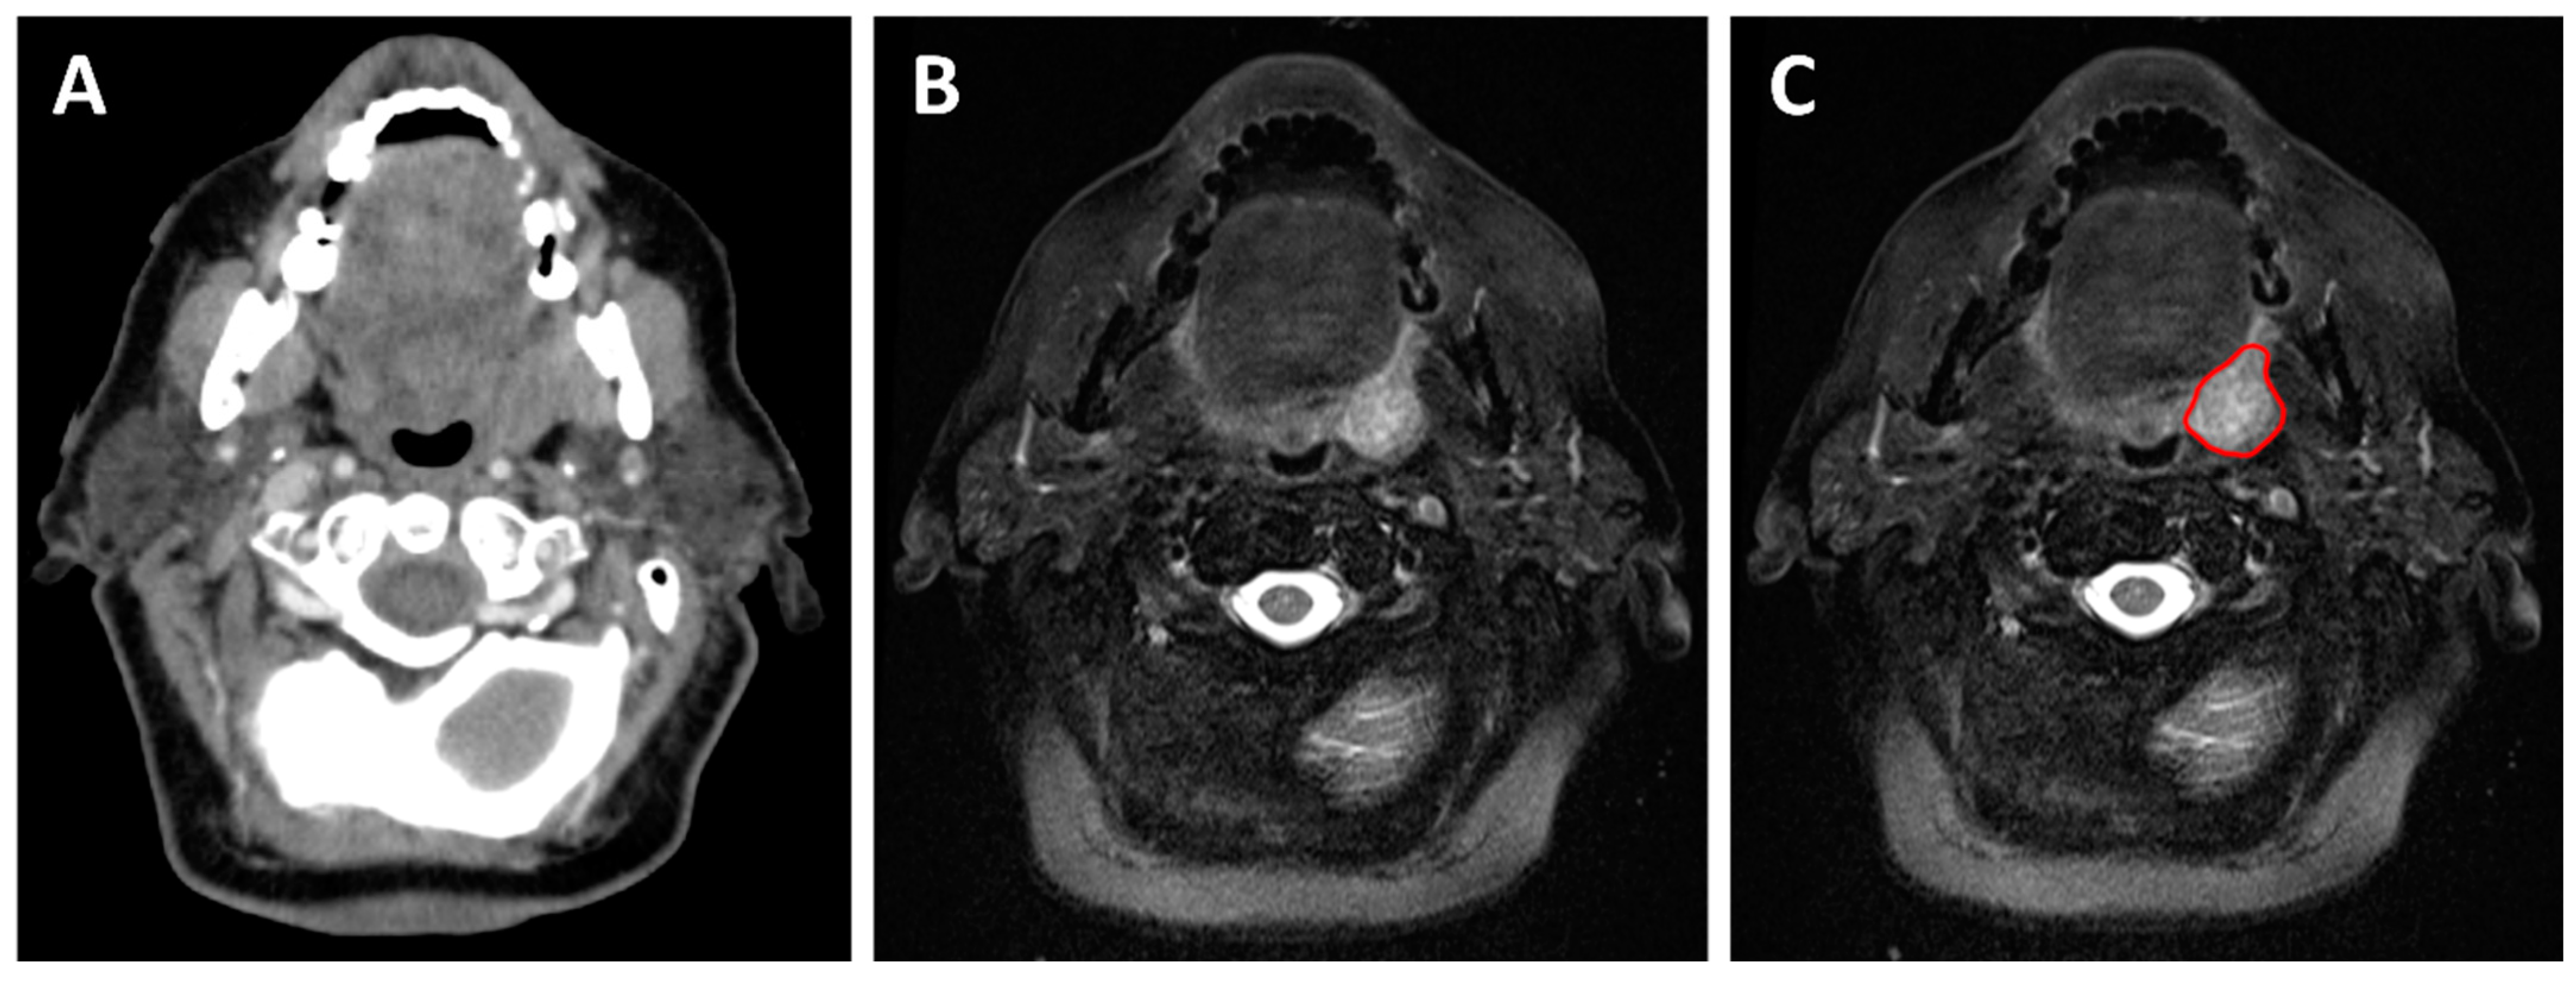

2.3. Treatment Planning

3. Treatment Adaptation

3.2.1. Anatomical Adaptation